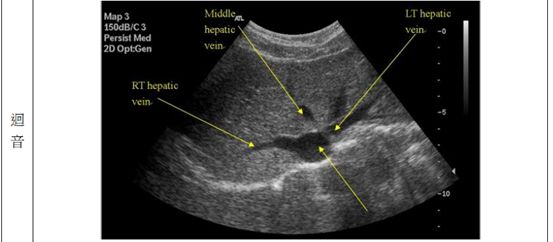

69.下圖為肝臟之橫切面,箭號所指為肝臟的那一個部位?

(A)左葉

(B)尾葉

(C)右葉

(D)左葉外側節